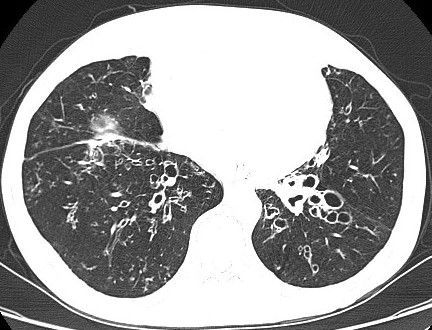

Las bronquiectasias son dilataciones anómalas e irreversibles de los bronquios cartilaginosos de tamaño mediano, que se acompañan de destrucción de los componentes muscular y elástico de la pared bronquial, generalmente asociadas a infección crónica. Son mas frecuentes en mujeres y la prevalencia aumenta con la edad. Pueden ser localizadas o a veces generalizadas en ambos […]